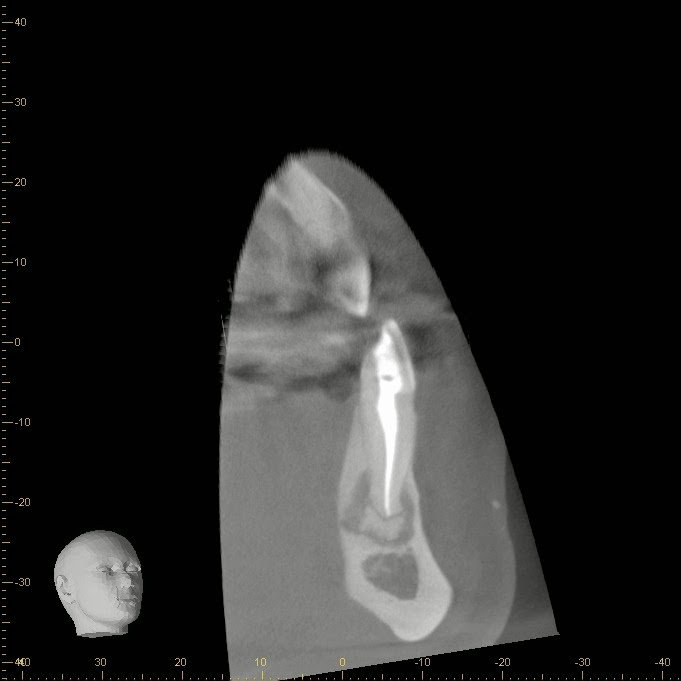

A 42 yr old, white, female presented for evaluation of #22. She was asymptomatic, with a prior RCT on #22. A large nodular, irregular, radiopacity found within a large radiolucent area on the periapical radiograph. Tooth is normal to palpation, percussion and probings.

DX: Prior RCT with possible periapical cemental dysplasia. Apical surgery recommended with biopsy.